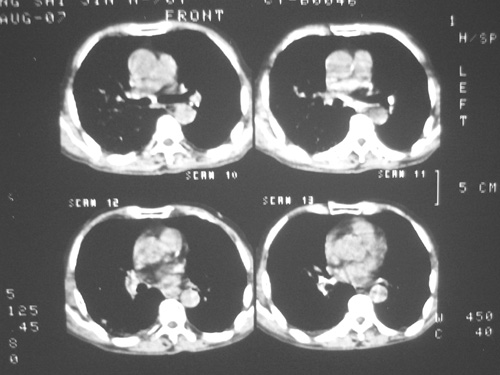

老年男性,70岁。煤矿工人20年。一周前咳嗽、发烧,拍x片考虑矽肺可能。始终咳嗽行ct检查,发现弥漫性病变,似感染但密度很高,细支气管肺泡癌无法排除,请老师给予指点。

患者病程较短,有明显咳嗽发热症状,结合病史考虑矽肺合并以间质为主的肺感染,肺泡癌先放下,抗炎再说

ct片与平片只相隔1周时间变化太大,结合临床应该首先考虑尘肺合并感染,肺泡癌变化不会这么快,